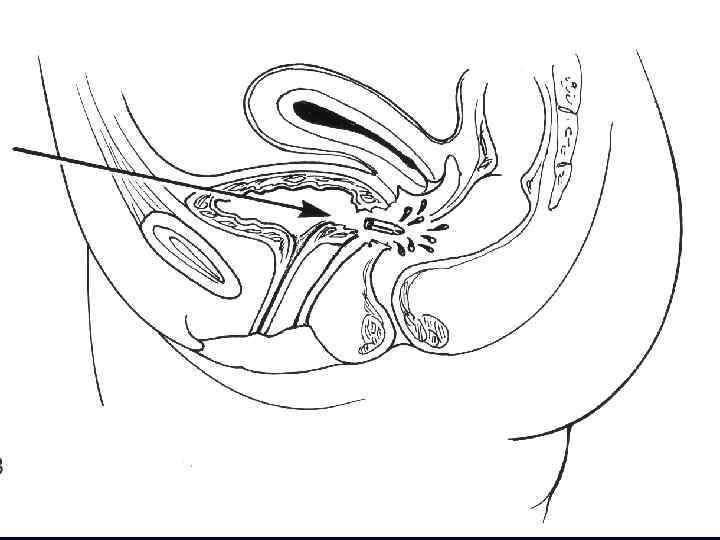

Механизмы травмы • Внебрюшинные разрывы, как правило, сочетаются с повреждением костей таза • возникают за счет разрыва связочного аппарата или повреждения мочевого пузыря костными отломками.

Механизмы травмы • Внутрибрюшинные разрывы обусловлены резким повышением внутрипузырного давления при наполненном мочевом пузыре • Чаще происходят в области верхушки ( «слабое место» ) • Имеет значение состояние стенки мочевого пузыря до получения травмы

Внутрибрюшинный разрыв Внебрюшинный разрыв